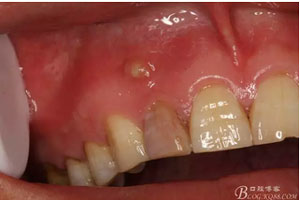

圖。一個月后患者復(fù)查: 唇側(cè)觀:11根尖區(qū)粘膜有一膿瘺,捫診溢膿,牙冠成灰褐色。根管治療無法治愈根尖病變,建議根管外科治療,患者同意手術(shù)。